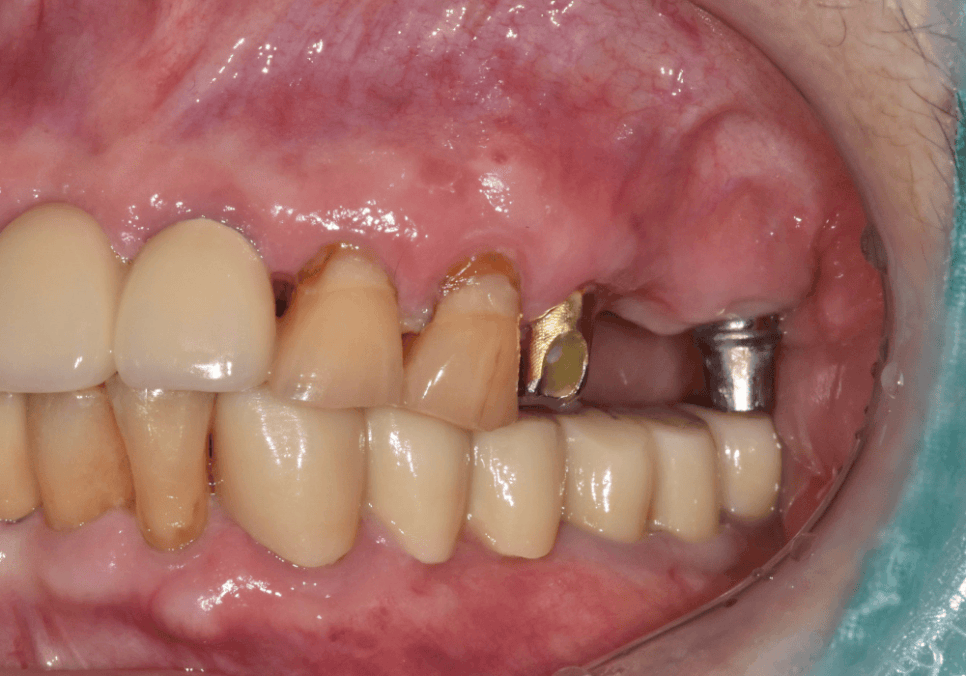

보철물이 떨어져서 오셨던 첫 내원

상일동 임플란트 심한 충치로 인한 치아 부러짐 해결한 사례

"왼쪽 위 어금니 임플란트

보철이 떨어졌어요."

이 환자분이 처음 저희 병원에 찾아주신

이유였습니다.

231109

우선 떨어진 임플란트 보철은

상태를 확인한 뒤

다시 잘 붙여드렸지만,

문제는 이곳저곳 충치가

다발적으로 있었다는 점이었습니다.

입안을 살펴보니,

#12(오른쪽 앞니) 부위에

치아 사이로 충치가 진행돼 있었습니다.

위 앞니(#11~22)는 브릿지 주변 잇몸에

염증이 꽤 심했고,

고름(배농)이 동반되는 상태였습니다.